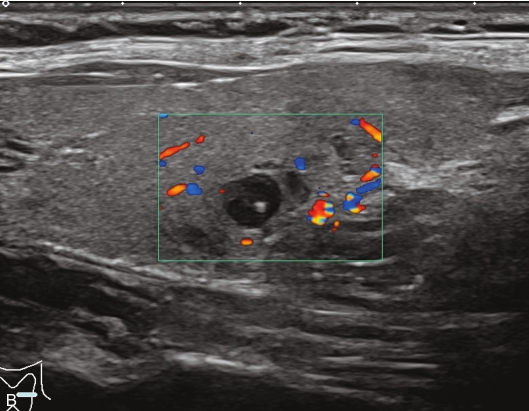

男性,64岁,体检发现甲状腺结节1天。体格检查:甲状腺无明显肿大。

甲状腺左叶中部实性中等回声,边缘光整,纵横比<1,内未见明显强回声,CDFI:结节内见血流信号,见图1-3-9。

图1-3-9 结节性甲状腺肿常规超声声像图

A.甲状腺左叶纵切面;B.CDFI血流图

甲状腺左叶中部结节15s开始增强。增强早期与周围正常甲状腺组织呈同步等增强,内部增强不均匀,增强后结节边界清,形态规则,周边可见环状高增强,增强晚期呈不均匀性低增强,见图1-3-10、ER1-3-5。

结节性甲状腺肿超声造影表现为病变多与周围正常甲状腺组织呈同步等或高增强,增强多较均匀,伴有囊性变者,内部可见无增强区,增强后结节边界清,周边可见环状增强,增强晚期呈等或稍高增强,也可呈稍低增强。

图1-3-10 结节性甲状腺肿超声造影图

A.增强早期结节呈同步不均匀性等增强;B.增强晚期呈不均匀性低增强